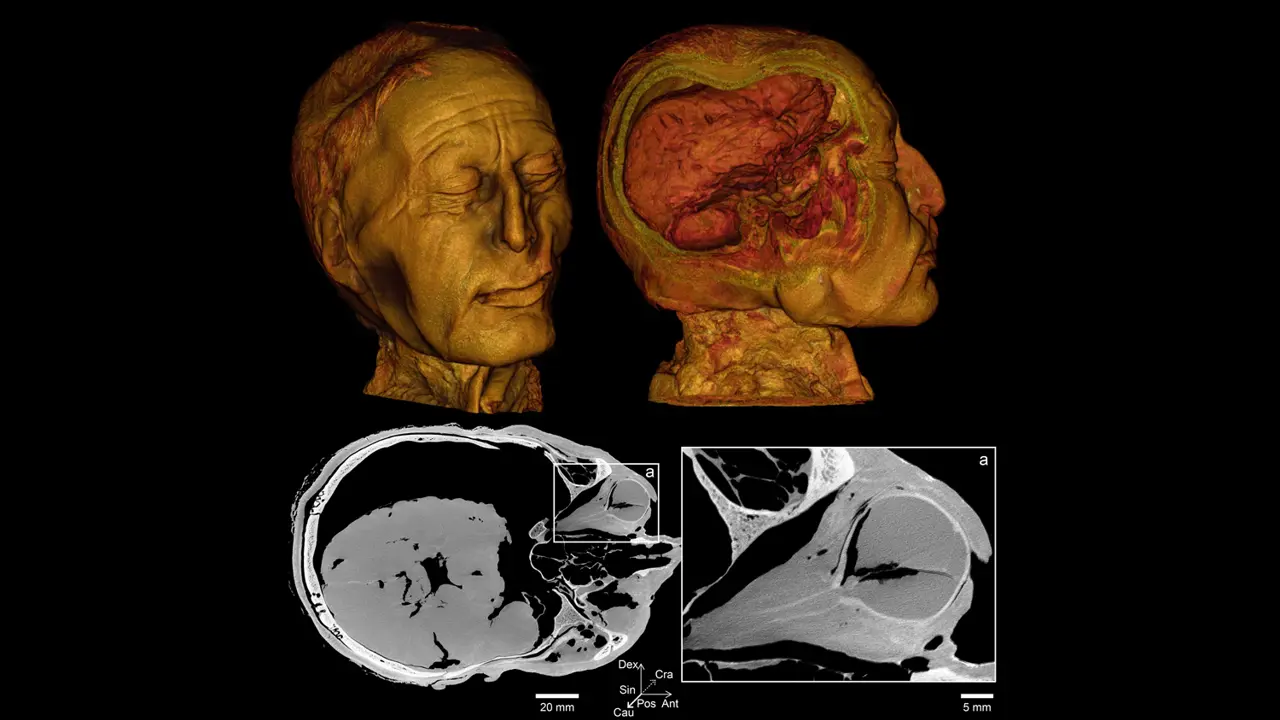

Nu har danske forskere fra Aarhus Universitet og Museum Silkeborg igen haft ham under videnskabelig granskning, denne gang med brug af både en klinisk CT-scanner og universitetets nye mikro-CT-scanner, som kan tage billeder med meget stor detaljeringsgrad. Helt præcist er de nye billeders opløsning 422 gange bedre end opløsningen i 2002.

Den nye mikro-CT-scanner adskiller sig fra universitetets andre scannere ved, at den både kan scanne små prøver ved ultrahøj opløsning og producere billeder af store genstande – så som et helt hoved fra et oldtidsmenneske. Igen er det da også hovedet, der har været genstand for undersøgelse, særlig med fokus på tænderne, halsen og øjnene.

Scanningerne har blandt andet afsløret, at Tollundmandens ene øje er fuldstændig intakt med form og synsnerver, mens hans andet øje er punkteret. De har også givet hidtil uset detaljerede billeder af hans tænder, som blandt andet kan fortælle noget om ernæringstilstand og eventuelle sygdomme, han led af.

Tollundmandens højre øje og hjerne er velbevaret. Øjet indeholder stadig linse og en intakt synsnerve. Foto: Aarhus Universitet og Museum Silkeborg

Fordi Tollundmanden har ligget i en syrlig mose i over 2000 år, er meget af hans knoglemineral udvasket. Det betyder, at kontrasten mellem knogler og det bløde væv er mindre end normalt.

Med en mikro-CT-scanner kan forskerne imidlertid opnå bedre kontrast på de forskellige væv og se mange detaljer.

Det har også været medvirkende til, at forskerne på baggrund af de nye scanninger for første gang endeligt har kunnet fastslå en dødsårsag.

Det har hidtil været formodet, at Tollundmanden blev hængt. Imidlertid har hidtidige undersøgelser i form af røntgen og scanning ikke været så nøjagtige, at man kunne afkræfte andre teorier, såsom at han kunne være blevet stranguleret.